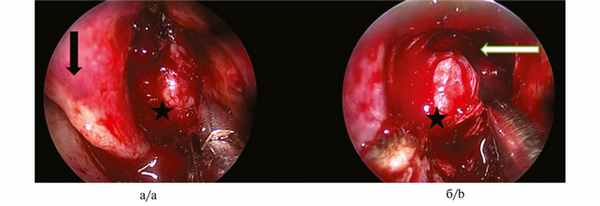

Первым этапом была выполнена септопластика, после чего стали обозримы задние отделы правой половины носа. Передняя стенка клиновидной пазухи была смещена опухолью, покрытой багровой слизистой оболочкой с характерным усиленным сосудистым рисунком, кпереди (рис. 1, а). Рис. 1. Эндоскопия полости носа (0 град. эндоскоп). а — начало операции: звездочкой показана ЮАОЧ, стрелкой — средняя носовая раковина; б — этап операции: звездочкой показана ЮАОЧ, стрелкой – полость правой клиновидной пазухи. Удалены задние отделы перегородки носа, передняя стенка клиновидной пазухи и межпазушная перегородка, после чего стала хорошо обозрима опухоль, плотно сращенная с нижней, задней, верхней и латеральной стенками клиновидной пазухи (см. рис. 1, б).

Затем опухоль была выделена единым блоком, на заключительном этапе была выделена латеральная часть опухоли и отсечена у основания. При этом отмечено выраженное кровотечение, которое было остановлено при помощи гемостатического материала Суржицель и тугой тампонады.